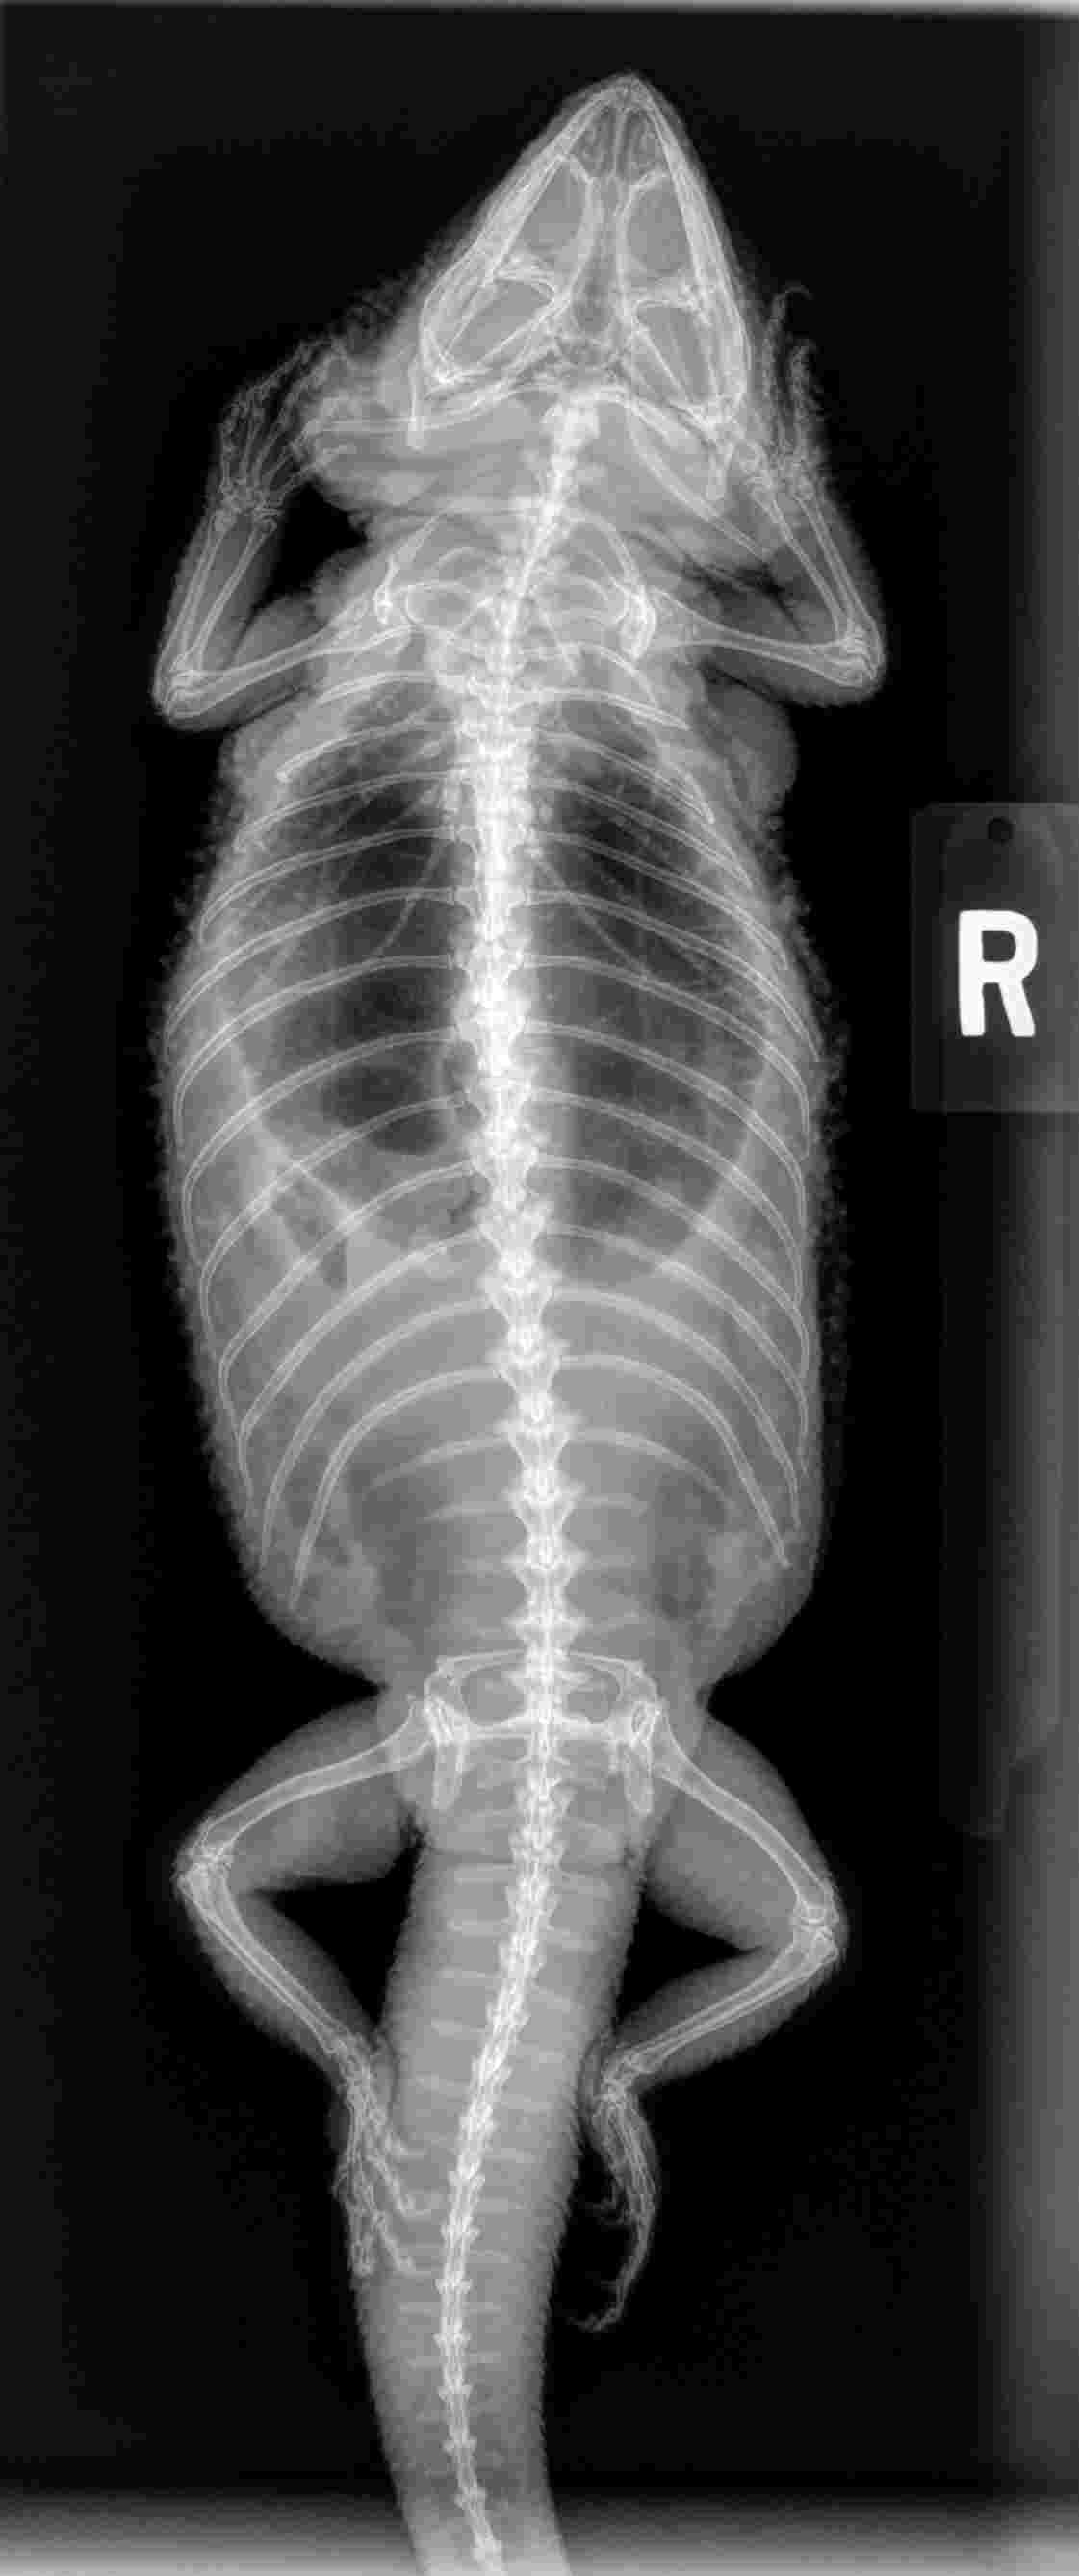

Pet's info: Reptile | Bearded Dragon | Female | unspayed | 7 years old | 1.2 lbs

Anemic bearded dragon, enlarged liver? What foods to give to help raise blood levels and health of liver. My vet thinks she might have a tumor on the liver or somewhere else. He is uncertain. Thanks so much

Dark leafy greens are fairly high in iron but if a liver tumor, will probably continue to bleed. A whole blood transfusion can provide red blood cells but also the constituents to possibly slow bleeding.